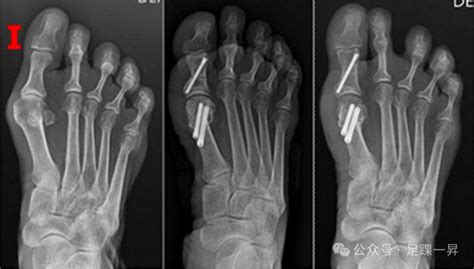

超微创拇外翻手术安全吗:深入解析其安全.